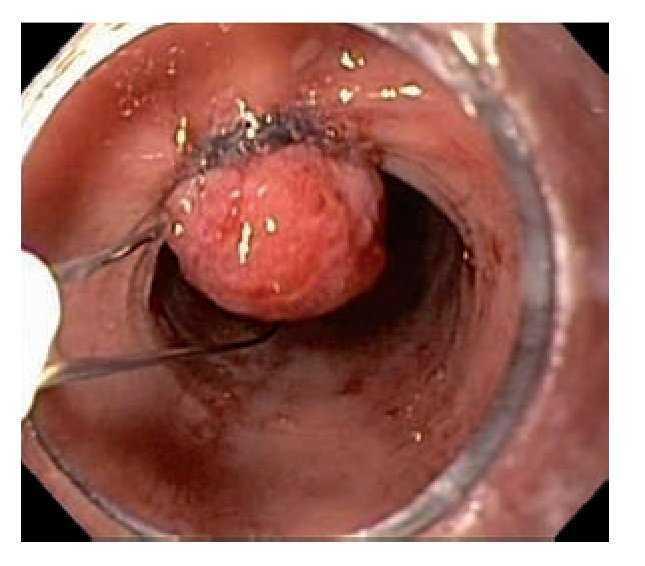

Hombre de 75 años de edad con pirosis de larga evolución y control médico irregular. Acude a realizarse endoscopia de tubo digestivo alto por hipo incoercible de reciente aparición. Durante el examen se observó mucosa sugestiva de esófago de Barret con lengüetas, la mayor de las cuales midió alrededor de 10 cm de longitud, con una circunferencia total de 7 cm (Praga C7M10), que involucraba los tercios medio y distal del esófago y sobre la cual se identificó una lesión polipoide de bordes irregulares de unos 10 mm de diámetro en el tercio medio del esófago que protruía hacia la luz (Figura 1). Se tomaron múltiples muestras para biopsia de dicha lesión que evidenciaron un adenocarcinoma bien diferenciado asociado al esófago de Barrett. Se realizó ultrasonido endoscópico (Olympus GFUCT140, Aloka alfa-5) que mostró engrosamiento focalizado de la pared esofágica de 3.4 mm x 4 mm que incluía mucosa y submucosa (Figura 2), además de observarse dos ganglios linfáticos subcarinales hipoecoicos redondos de 8 mm x 6 mm de los cuales se tomaron muestras para biopsia por aspiración con aguja fina que resultaron negativos para enfermedad maligna. En vista de la extensión de la lesión determinada por ultrasonido endoscópico, así como del riesgo de presentar metástasis ganglionares por el involucro de la lesión hasta la submucosa, pero debido al alto riesgo quirúrgico del paciente debido su edad y comorbilidades (hipertensión arterial sistémica, enfermedad isquémica reciente y enfermedad pulmonar obstructiva crónica avanzada), se decidió realizar una resección endoscópica de la lesión con el uso de capuchón transparente y ligas, previa elevación de la lesión con solución salina y epinefrina (Figura 3A, 3B), inyectando dicha solución en los bordes y la base de la lesión mediante aguja de escleroterapia. Después de la elevación, se realizó aspiración de la lesión en bloques con el capuchón transparente, una vez succionada una porción de la lesión se liberó una liga, después se introdujo el asa de polipectomía enlazando el tejido ligado y realizando el corte de esa porción de tejido. Se recuperaron con red tres piezas quirúrgicas de un tamaño cercano de 5 mm, cada una las cuales fue extendida con alfileres en una tabla, introducidas en formol y enviadas a estudio histopatológico, el cual reportó adenocarcinoma moderadamente diferenciado con ulceración focal, con infiltración de la lámina propia y la muscular de la mucosa, pero sin invasión de la submucosa ni invasión vascular; los bordes quirúrgicos fueron negativos para neoplasia. Dos meses después del procedimiento, el paciente se encuentra asintomático y en buenas condiciones generales (Figura 3C).

Figura 1. Esófago de Barrett y lesión polipoide en esófago.